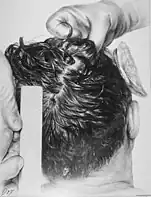

At 7:35 pm EST on November 22, Humes and Boswell removed Kennedy's body from his bronze casket and began the autopsy.[16] Around two dozen people, including military officers, were in attendance.[17][note 3] Admiral Burkley urged the doctors to expedite the autopsy: "all we need is the bullet". Drs. Humes and Boswell, however, argued for a thorough and complete autopsy but temporarily submitted.[23] Medical personnel took photographs—both black and white and color—and X-rays of his head.[23] The X-rays revealed around 40 small bullet fragments along the bullet's trajectory through Kennedy's head, with two large enough to be of interest to investigators. Drs. Humes and Boswell then contacted wound ballistics expert Lieutenant Colonel Pierre Finck of AFIP for assistance.[24] However, they grew tired of waiting and removed the two fragments.[25] They also extracted Kennedy's entire brain and placed it into formaldehyde for later study. Finck arrived soon thereafter and examined the head wound with Boswell and Humes.[26]

- The gunshot wound to the back of the president's head was described by the Bethesda autopsy as a laceration measuring 15 by 6 millimetres (0.59 in × 0.24 in), situated to the right and slightly above the external occipital protuberance. In the underlying bone is a corresponding wound through the skull showing beveling (a cone-shaped widening) of the margins of the bone as viewed from the inside of the skull.[38]

- The large and irregularly-shaped wound in the right side of the head (chiefly to the parietal bone, but also involving the temporal and occipital bone) is described as being about 13 centimetres (5.1 in) wide at the largest diameter.[38]

- Three skull bone fragments were received as separate specimens, roughly corresponding to the dimensions of the large defect. In the largest of the fragments is a portion of the perimeter of a roughly circular wound presumably of exit, exhibiting beveling of the exterior of the bone, and measuring about 2.5 to 3.0 centimetres (0.98 to 1.18 in). X-rays revealed minute particles of metal in the bone at this margin.[38]

- Minute fragments of the projectile were found by X-ray along a path from the rear wound to the parietal area defect.[39]